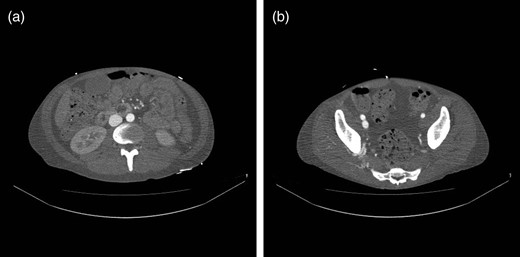

Endovascular treatment of the AV fistula was performed in the following day. The contralateral femoral artery was accessed, angiography showed the fistula (Fig. 2a) and a stent-graft (Fluency, Tempe AZ, USA) was implanted in the cranial part of the right superficial femoral artery, covering the fistula (Fig. 2b). Treatment eliminated the arterial phase contrast filling in the veins. The patient recovered rapidly and was discharged 1 month later, after a total hospital stay of almost 8 weeks. Intravenous antibiotic treatment (cloxacillin and ciprofloxacin) continued until discharge. After discharge, he received oral trimethoprim sulfamethoxazole for another 4 weeks. At last follow-up, he showed no signs of recurrent infections, but was still intermittently abusing drugs.

(a) Angiography demonstrating an AV fistula between the right superficial femoral artery and the femoral vein. (b) A stent-graft is implanted in the cranial part of the right superficial femoral artery, sealing the AV fistula.